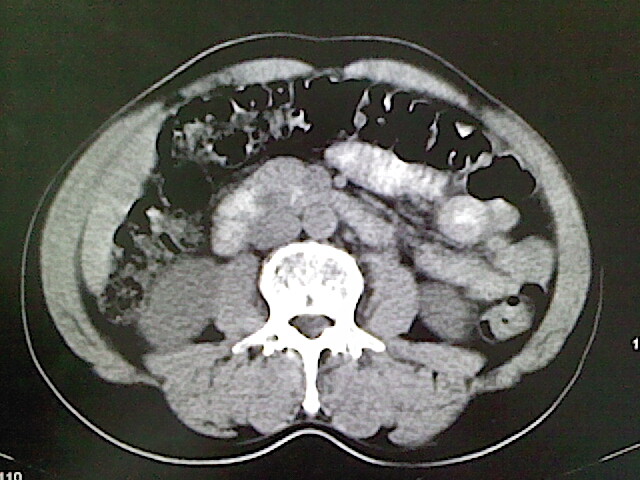

标题: CT18630:男,54岁,乙肝,大家看怎么样?

男,54岁,乙肝,大家看怎么样?

未见明显异常

未见明显异常!(另:患者有乙肝病史,应定期做彩超检查!)

肝脏的要有增强敢说话

医学影像诊断的基本原则之一是密切结合临床,请你提供简明扼要的病史。

未见明确异常;建议必要时行ct增强扫描检查。